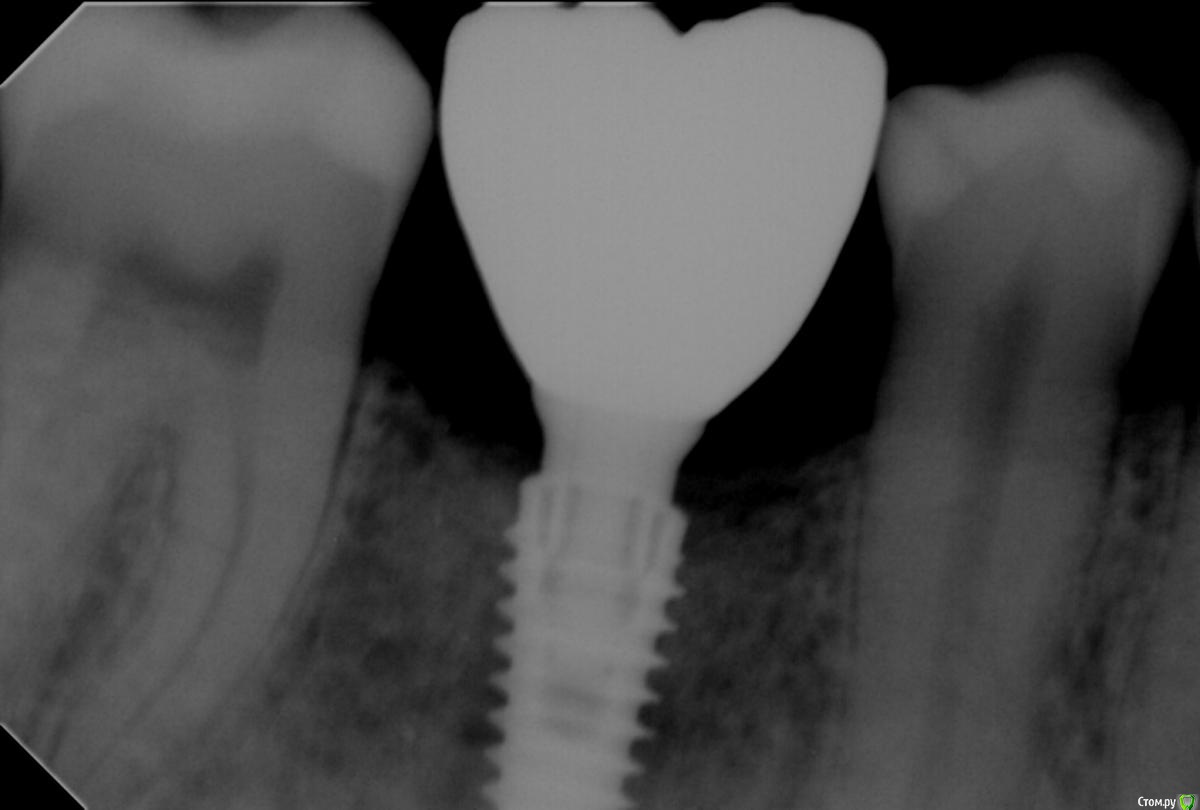

Freelancer1981 Опубликовано 5 сентября, 2016 Поделиться Опубликовано 5 сентября, 2016 Уважаемые форумчане кто работал(работает)на системе Anyridge?Суть вопроса-до сего момента работал на системе Необиотек и Эниван(Мегаджен) проблем не было.Сегодня пытался прикрутить постоянную коронку на имплант(4мм диаметр)Anyridge-не садится.до этого была времяха-все ок,лаборатория впервые вытачивала основание постоянное для этой системы,на модели сидит все ок,во рту не садится,ошибки в слепке исключена,аналог(базовый синего цвета) прикручивал сам.пробовал на модель с посиоянной короник посадить времяху-садится как там и была.у меня такое ощущение что диаметр аналога не совсем состтветствует диаметру импланта,можт я чего не знаю-повторяюсь на эту систему постоянную коронку делали впервые.у меня уже много пациентов котрые ходят с времяхами на этой системе уже как то стремно делать постоянные а вдруг опять та же ерунда.. Ссылка на комментарий